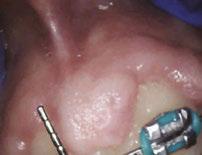

Over 10 years ago, we began Orthotropic® treatment for a 5 year, 3-month-old boy with a diagnosis of Pierre-Robin Sequence, Obstructive Sleep Apnea (OSA), and Failure to Thrive (Figure 1). With lack of forward development of the face com-

monly seen in Pierre-Robin patients, his airway was compromised, resulting in OSA. The Failure to Thrive diagnosis likely resulted from insufficient growth hormone being released during the deeper stages of sleep. This treatment began before any permanent teeth erupted. Our goal was to eliminate OSA.

Orthotropics® uses removable appliances to laterally expand the upper arch while simultaneously advancing the upper anterior teeth to their proper place in the face. Then the mandible is developed forward. Orthotropics® is my preferred treatment in cases like this because it negates the head gear-effect producing better facial balance5 and also can result in substantial airway improvements (Figure 2).6

This young boy had great parental support and was very compliant during the treatment. A posttreatment sleep test showed no signs of sleep apnea.7 Failure to Thrive was also overcome. Now at 17 years old, this patient is 5 ft. 7in. tall and is still growing. I believe that improved breathing and sleep has resulted in an increase in HGH production which allowed him to resume normal growth. He’s an aggressive tennis player with a big smile and no return of his OSA (Figure 3). Thankfully, he’s an excellent student with no evidence of brain damage from his early OSA diagnosis.

Figure 1: Pretreatment gallery Figure 3: Today, he’s a tennis player Figure 2: Pre- and posttreatment airways